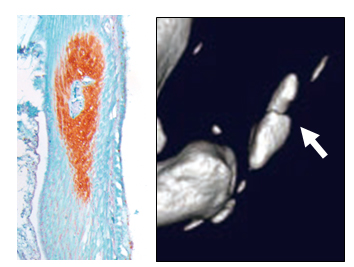

ノックアウトラットをさらに詳細に解析すると、出生後まもなくアキレス腱が骨化することが明らかになりました。改変された遺伝子はMkxという腱・靭帯の中心的な遺伝子で、その遺伝子の欠損でラットのアキレス腱の骨化を引き起こすことがわかりました(図4)。

図4. アキレス腱の骨化(左、中心の赤い部分と右の➡の部分)